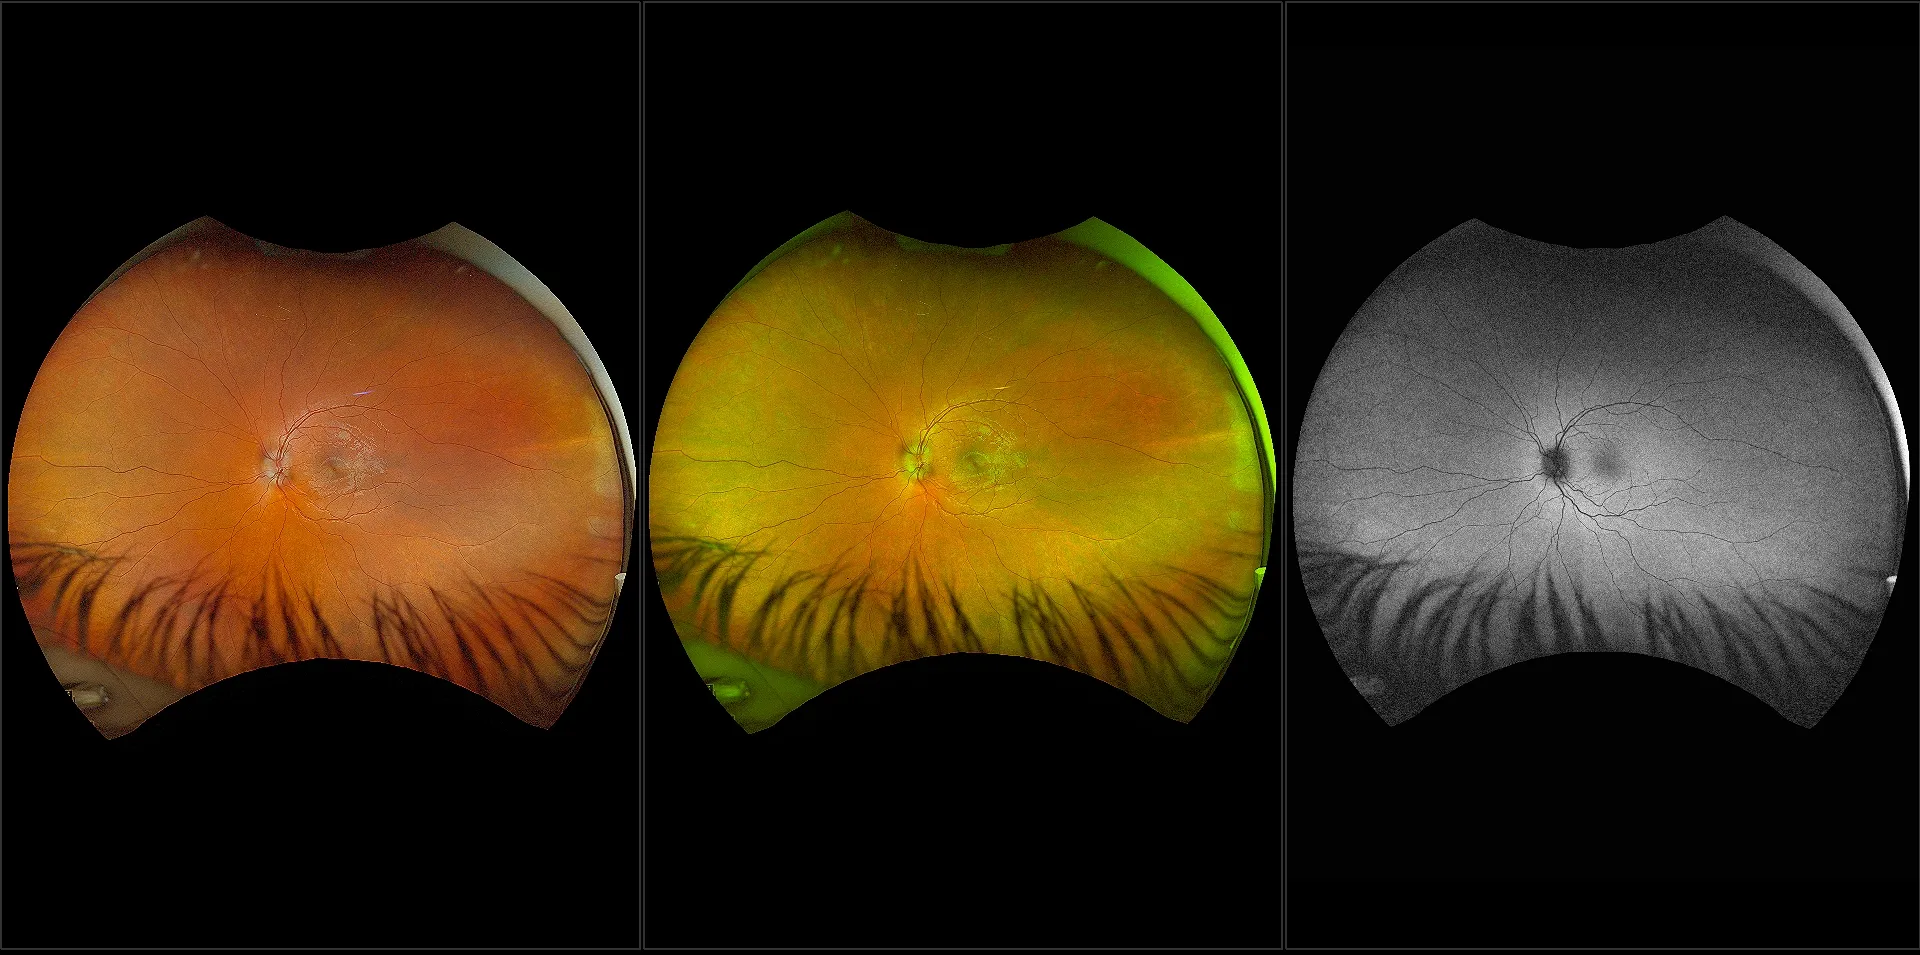

optomap® Recognizing Pathology

This material is designed as a searchable reference resource to support clinical decision-making. The information contained here should be used as general guidance when viewing optomap and OCT images from Optos devices. The differential diagnosis should be made under the direction of the responsible physician. These images were taken on the latest ultra-widefield optomap devices.

The Cases and Images

optomap Recognizing Pathology is searchable by pathology and/or optomap image modality. You may search by multiples of each selection. Each individual case is represented by the accompanying thumbnail image. Most cases include several different optomap image modalities. To view a full description of the case, please click on the thumbnail. Each image in the case will be made available through our OptosAdvance software which provides multi-dimensional visualization of digital images to aid in the analysis of anatomy and pathology. Support and pathology definitions can be found by selecting one of the buttons, above. Should you have questions, please complete the form below.